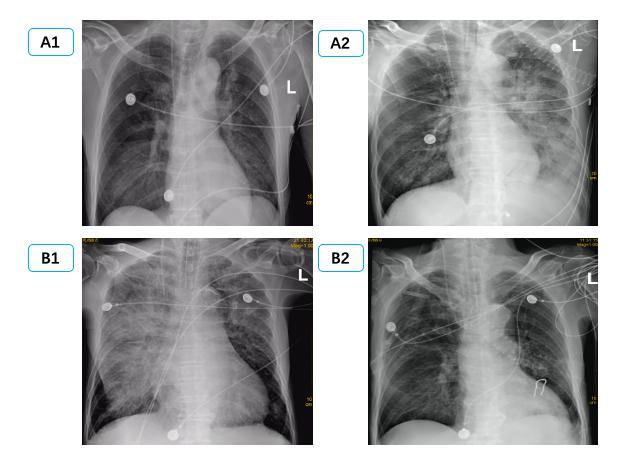

(C1、C2为同一患者,右侧PE,男,56岁,冠状动脉搭桥术后,C1为咳嗽咳痰1周入院时,C2为抗感染治疗14 d后。D1、D2为同一患者,左侧PE,女,32岁,眼眶下局麻后心脏骤停,D1为心脏骤停后3 h,D2为心脏骤停后24 h。) 图 2 单侧肺水肿CT表现 Fig 2 Manifestations of unilateral PE on CT

通过病历系统回顾性分析2018年1月至2021年1月,共纳入314例患者,其中男性179例,女性135例,年龄18~97岁[(58.8±16.9)岁]。单侧PE患者共14例,发病率4.5%,男性10例,女性4例; 其中以右侧为主单侧PE 11例(78.5%),左侧PE患者3例(21.5%)。1例单侧PE呈右肺上叶局限性分布,(见图患者C),1例单侧PE以左下肺为主(见图患者A),其余单侧PE分布无明显肺段特点。

在本次试验中单侧PE发生率为4.5%,高于国外心内科单侧PE 2.1%发病率[2]。同时本次14例单侧PE中,主要(11例,78.5%)为右侧PE,与国外研究类似(16例,89%)[2]。本研究中,两组间左心室射血分数、左心房前后径、左心室舒张末内径等心脏超声参数均差异无统计学意义,与既往研究类似。同时该研究发现单侧PE患者重度二尖瓣反流比例高达100%[2]; 提示二尖瓣反流是导致单侧PE的主要原因。本研究中重度二尖瓣反流在单侧PE组发生率显著高于双侧PE组,35.7% vs 14.0%,但显著低于前述研究,可能与患者纳入标准有关,有5例(35.7%)因心室颤动等原因导致心脏骤停。其中如图 2中D患者,女,32岁,眼眶下局麻后心脏骤停。心脏骤停后3 hCT提示左肺弥漫渗出,但复苏8 h后查心脏超声无明显二尖瓣反流,考虑与心脏骤停冠脉缺血导致暂时性二尖瓣反流有关[25-26],因此24 h后复查CT左肺单侧PE完全消失。

除考虑二尖瓣偏心反流导致单侧或单支肺静脉压力升高,回流受阻,还可能与双侧肺静脉回流角度、大小有关。研究显示左心房入口处,右侧肺静脉相比左侧肺静脉其内径、横截面积均更大[27],同时右肺静脉与二尖瓣反流的角度更小,因此在二尖瓣导致的单侧PE以右侧为主[2],尤其是右上叶为主[9, 11],部分患者PE表现非常局限,常常误诊为肺部感染[9, 28],如图 2中C患者。但本研究中心脏骤停患者,心肺复苏按压时双侧肺静脉回流阻力是否有影响目前尚不明确。